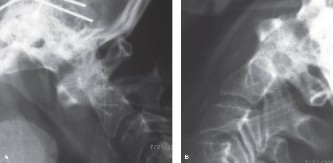

Radiographic and Computed Tomography Evaluation

Initial trauma radiographs demonstrated a loss of anterior and middle column height at L1, with a focal kyphotic deformity. However, plain films are vastly insufficient for definitive surgical planning in thoracolumbar trauma. A high-resolution, fine-cut Computed Tomography (CT) scan of the entire spine was obtained. The CT images confirmed an L1 burst fracture with severe comminution of the vertebral body. Sagittal and axial reconstructions revealed 50% canal compromise secondary to a large retropulsed bone fragment originating from the posterosuperior aspect of the L1 vertebral body. Furthermore, the CT demonstrated 25 degrees of segmental kyphosis measured from the superior endplate of T12 to the inferior endplate of L1.

Magnetic Resonance Imaging and the Posterior Ligamentous Complex

To definitively assess the integrity of the soft tissue stabilizers and the neural elements, a Magnetic Resonance Imaging (MRI) scan without contrast was performed. Historically, textbooks propagated the "50-50-25 rule," suggesting that a burst fracture was inherently unstable if it exhibited >50% canal compromise, >50% loss of vertebral body height, or >25 degrees of kyphosis. Modern spine trauma surgery has largely debunked this rigid radiographic dogma. We now understand that these bony metrics alone do not dictate mechanical instability. The true arbiter of stability is the Posterior Ligamentous Complex (PLC).

The MRI, particularly the Short Tau Inversion Recovery (STIR) and T2-weighted sagittal sequences, provided the definitive diagnosis. The images demonstrated profound hyperintensity and discontinuity of the ligamentum flavum, the interspinous ligaments, and the supraspinous ligaments at the T12-L1 level. The facet joint capsules were also disrupted, indicated by fluid within the joints. This complete failure of the PLC means the posterior tension band is gone. Regardless of the bony parameters, this spine cannot resist physiological flexion loads. If treated non-operatively, this injury will inevitably lead to progressive kyphosis, delayed neurological deficit, and intractable pain.